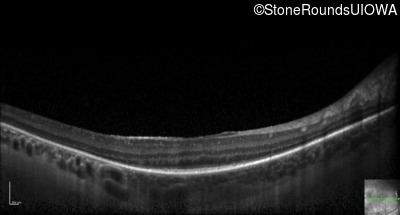

Optical Coherence Tomography - Left - 20/32 -1

Exemplar / OCT Stack

OCT Stack